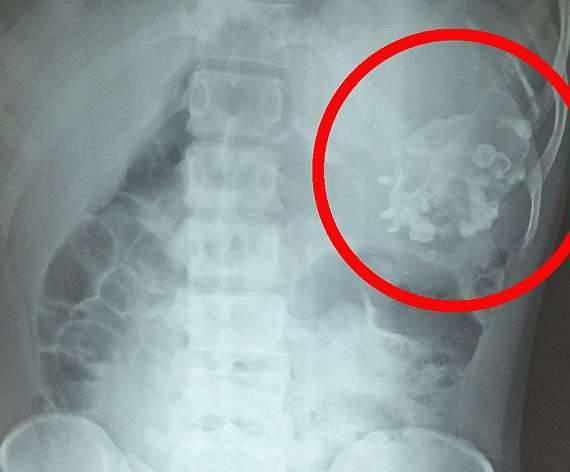

▼医生通过X光检测,发现他体内存在异物。

库马尔到医院检查时,医生为他做了X光检测,发现他的体内藏有一个2.5公斤重的异物。大家都以为这是个肿瘤,但手术时却看到异物上有牙齿,还有很多毛髮。医生确定这是一个「胎中胎」,已经在库马尔的体内寄生了18年。